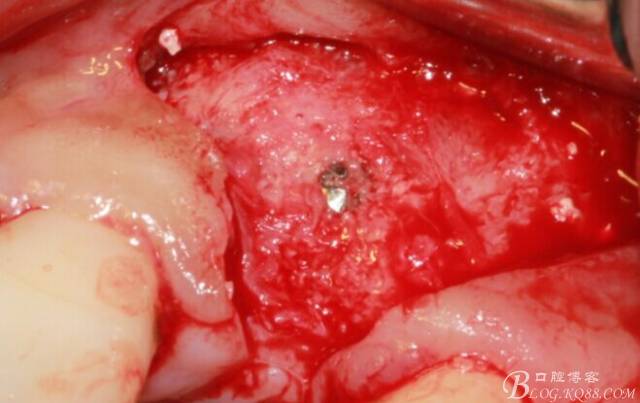

翻開后驚喜的發(fā)現(xiàn),術(shù)區(qū)成骨非常好,去除部分骨才暴露那顆長鈦釘。

取出影響種植入路的長鈦釘。

擴孔。